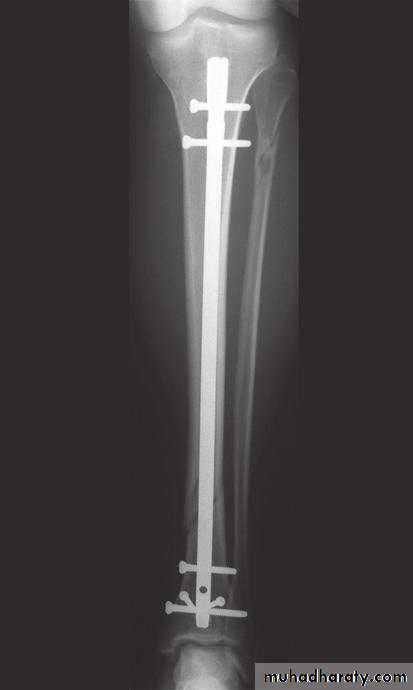

1-OSTEOTOMY:Osteotomy may be used to correct deformity, to change the shape of the bone, or to relieve pain in arthritis by redirecting the load.2-BONE FIXATION (internal or external fixation).

Internal and External fixation